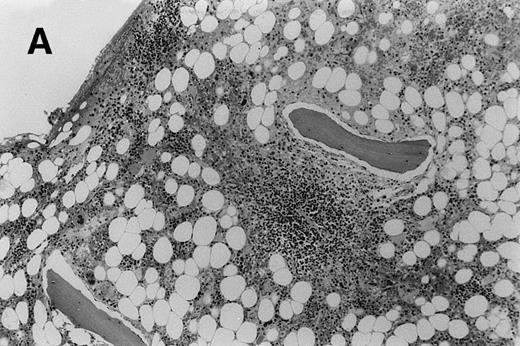

In 39 patients there was concordance between the PET scan and the routine iliac crest marrow biopsy (Table1). In 26 patients there was no increased FDG uptake within the marrow and the biopsy histology was normal. In 13 patients increased marrow FDG uptake was associated with histological evidence of marrow infiltration by lymphoma in the routine iliac crest biopsy (11 NHL, 2 HD). Two of these patients demonstrated the sensitivity of the PET technique: 1 patient with follicular centroblastic centrocytic lymphoma who had low-volume, nodular marrow disease (Fig 3A) and another patient with T-lymphoblastic lymphoma, who had only 15% blast cells on marrow aspirate and a modest interstitial infiltrate on trephine section (Fig3B). Both had the marrow disease identified by increased FDG uptake. Only 1 of the 5 patients with focal FDG uptake in an otherwise normal marrow had, by chance, an area of high FDG accumulation (“hot spot”) biopsied by the routine marrow trephine, which confirmed NHL.

Trephine biopsy sections. (A) A patient with follicular centroblastic centrocytic lymphoma stained with hematoxylin and eosin showing low-volume, nodular disease (original magnification ×100). (B) A patient with T-lymphoblastic lymphoma stained with anti-CD3; cells with dark cytoplasm are CD3+ (original magnification ×400). These photomicrographs show the low level of lymphoma infiltration which in both cases was detected by PET.